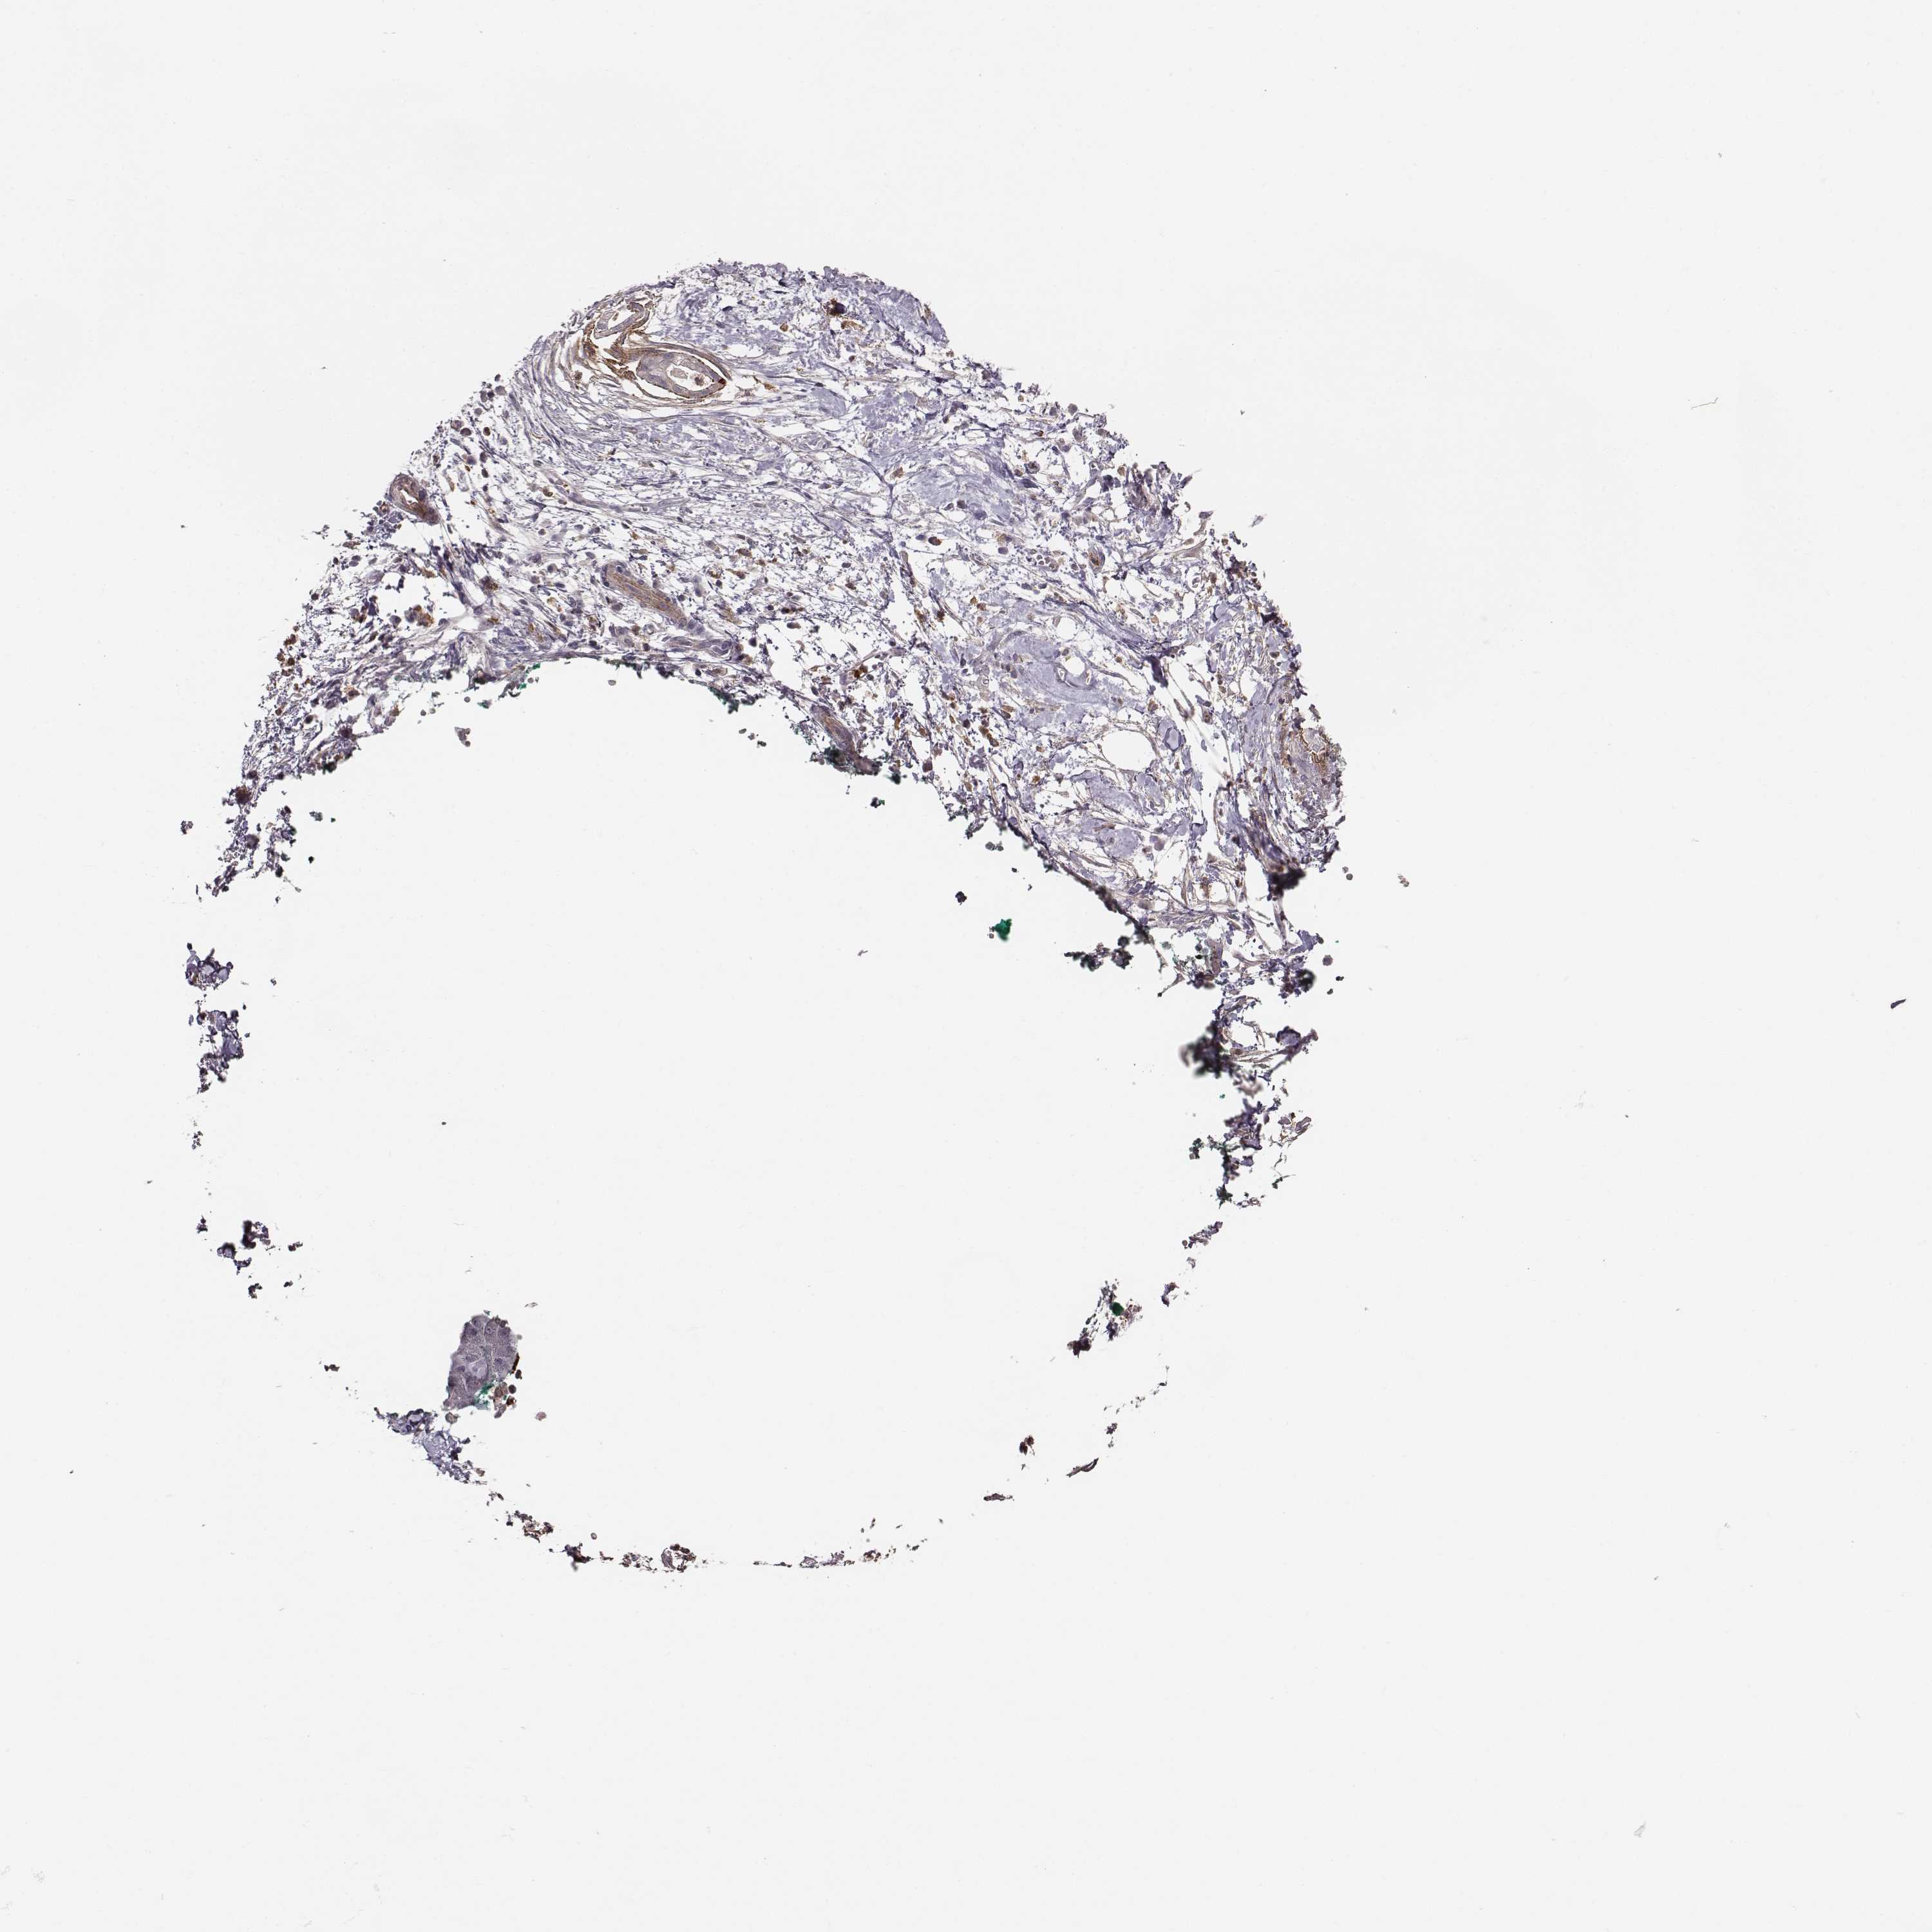

PANCREATIC CANCER - Protein expressioni

A mouse-over function shows sample information and annotation data. Click on an image to view it in a full screen mode. Samples can be filtered based on level of antibody staining by selecting one or several of the following categories: high, medium, low and not detected. The assay and annotation is described here.

Note that samples used for immunohistochemistry by the Human Protein Atlas do not correspond to samples in the TCGA dataset.

Antibody stainingi

Antibody staining in the annotated cell types in the current human tissue is reported as not detected, low, medium, or high, based on conventional immunohistochemistry profiling in selected tissues. This score is based on the combination of the staining intensity and fraction of stained cells.

Each image is clickable and will lead to virtual microscopy that enables deeper exploration of all samples and also displays staining intensity scores, fraction scores and subcellular localization as well as patient and tissue information for each sample.

Antibody HPA004835

Antibody HPA073497

Antibody CAB009321

Antibody CAB075747

Staining

Adenocarcinoma, NOS